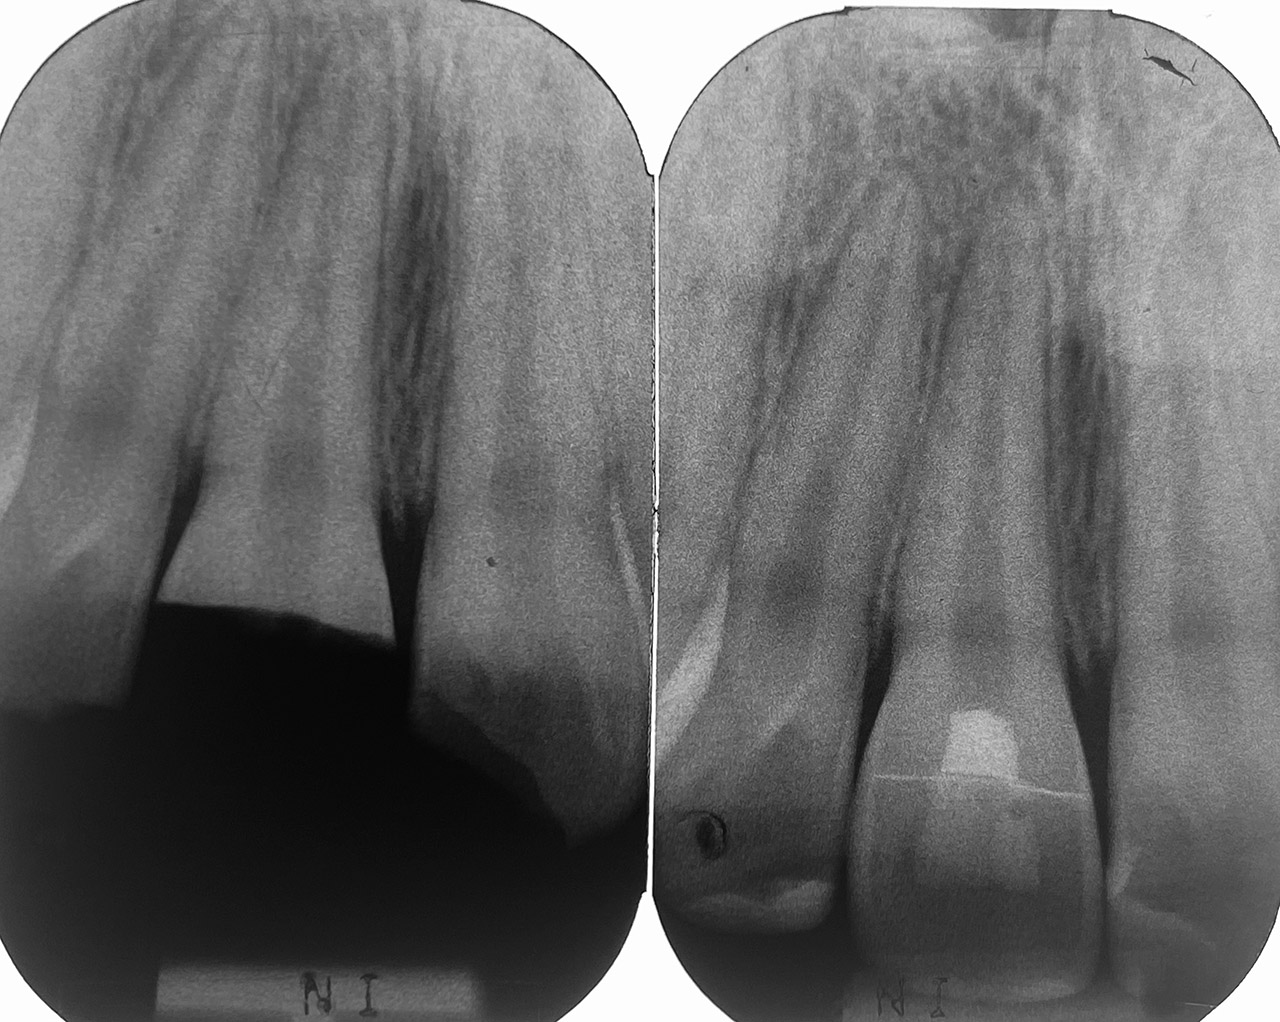

Nach Unfall mit E-Scooter unbefriedigendes Ergebnis der Erstversorgung (alio loco). Therapievorschlag: Stiftzähne?

Unsere minimalinvasive Therapie: Revision der Wurzelbehandlungen, danach internes und externes Bleaching, adhäsive Kunststoffüllungen in Schichttechnik. (Titel meiner Diplomarbeit 2003 “Die Vermeidung von Extraktion und Wurzelspitzenresektion durch zeitgemässe Endodontie in der Privatpraxis”)